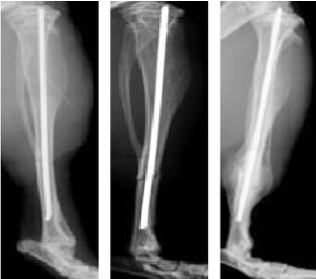

部分结果展示

X-ray